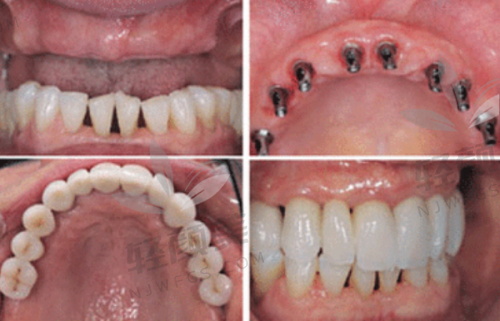

我年纪不算大,但是因为之前不注意口腔卫生,又特别爱吃甜食,牙齿状况一直不太好。前几年开始,牙齿就陆陆续续出问题,不是牙疼就是掉牙。到后来,半口牙都没了,吃饭只能吃点软乎的东西,稍微硬一点的就嚼不动,整个人的营养都跟不上,脸色也越来越差。而且因为缺牙,说话还漏风,真的特别影响形象和生活质量。我就想着必须得把牙齿问题解决了。

我提前在网上预约了时间,到了医院之后,前台的小姐姐特别热情,特别快就帮我安排了医生。给我看牙的是一位经验多的医生,他先给我做了全方面的口腔检查,包括拍X光片、取牙齿模型等等。然后根据我的检查结果,给我详细地分析了我的牙齿状况,还给我介绍了半口吸附性义齿和种植牙这两种修复方案。

医生说半口吸附性义齿比较适合我目前的情况,它是利用口腔黏膜和义齿基托之间的吸附力来固定义齿,佩戴比较舒适,而且价格相对种植牙来说要便宜一些。种植牙虽然成效更好,更接近自然牙,但是价格比较高,而且对牙槽骨的条件要求也比较高。我听了医生的介绍之后,觉得半口吸附性义齿更适合我,就决定选择这个方案。

确定方案之后,医生就开始给我制作义齿。整个制作过程大概花了一个多星期,期间我去了几次医院进行试戴和调整。医生特别有耐心,每次都会根据我的佩戴感受进行调整,直到我觉得舒适为止。

五、佩戴义齿后的感受

刚戴上义齿的时候,会有一点不习惯,感觉嘴里有个东西,说话也有点大舌头。但是适应了几天之后,就好多了。现在我已经完全适应了义齿,吃饭也香了,什么东西都能吃,再也不用羡慕别人吃美食了。而且义齿的稳定性良好,不会轻易松动或者脱落,说话也不会漏风了,整个人都自信了特别多。